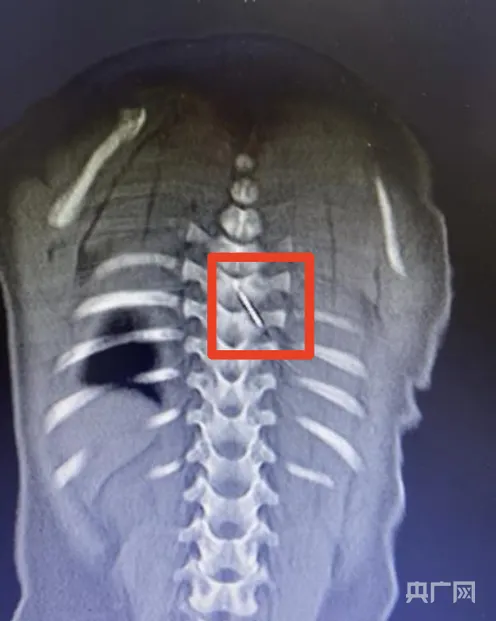

央广网合肥12月19日消息(记者 刘浩)12月5日深夜,一名仅9个月大的男婴因一根长约3厘米的缝衣针扎入脊柱,被紧急送往安徽省儿童医院救治。影像下

深夜时分,具体是2024年12月5日的深夜,一名年龄仅仅只有9个月大的男婴,被送到了安徽省儿童医院。经过检查发现,有一根长度大约为3厘米的缝衣针,刺入了他后背的脊柱区域。那根针是裹在被子里面的,在孩子睡觉的时候刺入的,并且随着身体的活动逐渐深入进去。

情况处于极度危急的状态之中,那细细的针尖,现已刺入到了脊柱的内部位置,紧紧挨着极为关键重要的脊髓,脊髓乃是神经中枢所在之处,一旦遭受损伤,便极有可能致使孩子出现永久性瘫痪的状况,此时医院快速地启动了最高级别的应急响应措施。

在当天凌晨2点那一时刻,一个由儿童骨科、麻醉科、重症医学科以及影像科专家共同构成的团队,马上开展了行动。这个团队先是借助三维CT影像,精准地重新构建了缝衣针在人体内的具体所处位置以及走向状况,进而看清了它同周围每一根血管、每一条神经之间的相邻关系。